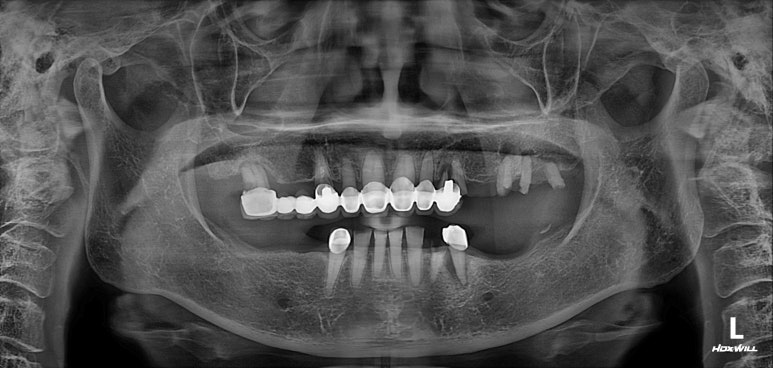

엑스레이는 지난 내원 때 찍었던 것인데, 한가지 알 수 있는 것은?

다행히도 잇몸뼈가 건강하고 많아서 충분히 임플란트로 치료가 가능하다는 것!!

아래턱에 뼈이식을 하면서 임플란트 1차 수술을 먼저 시행했습니다.

보시면 아래턱뼈에 총 5개의 임플란트를 심어드렸습니다.

사실 7개의 임플란트를 심어드려야 아래턱 치아 총 14개를 만들어드릴 수 있습니다만,

종종 경제적인 이유로 12개를 만들어드리는 것을 목표로 치료계획을 세우곤 합니다.

일반적으로 위턱뼈가 다소 무르고, 아래턱뼈가 보다 딱딱하기 때문에 위턱에 식립한 임플란트의 치유기간이 1달정도 깁니다. 그래서 위턱뼈 임플란트 수술을 먼저 합니다만, 이번 환자분의 경우 아래턱은 이미 치아가 발치되어 있던 상태셨기 때문에 아래턱 임플란트 수술을 먼저 했습니다.